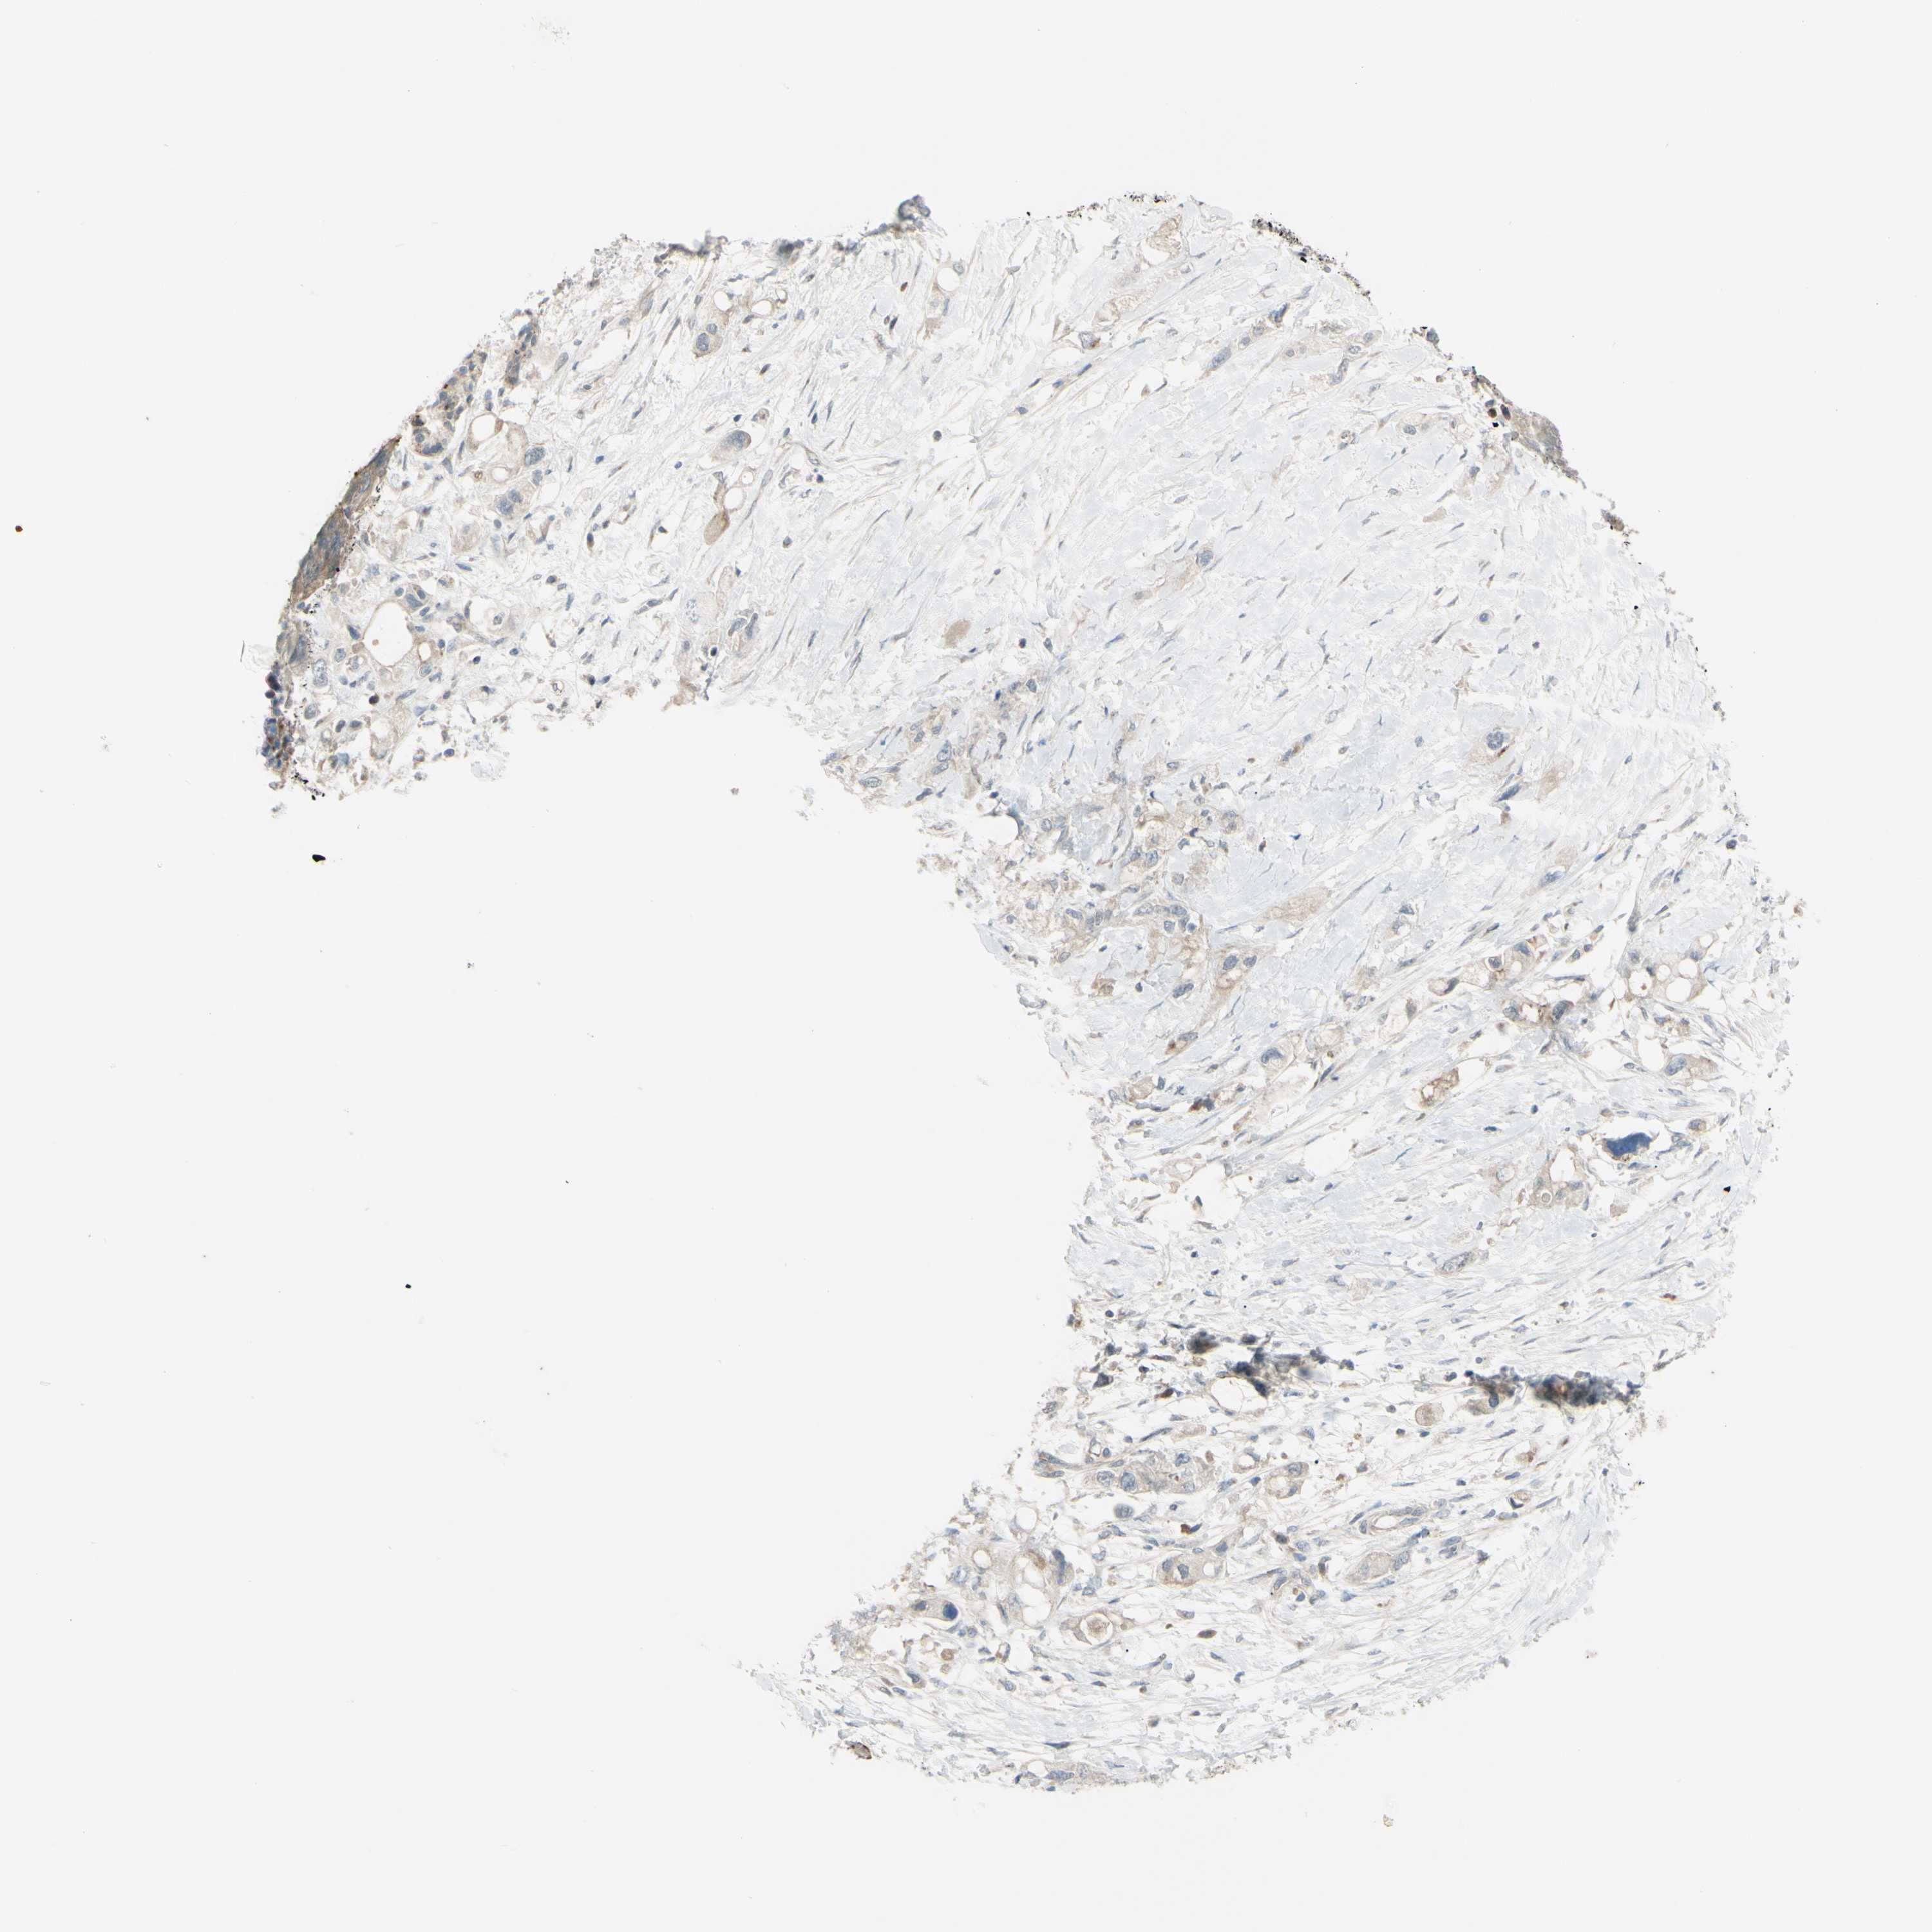

PANCREATIC CANCER - Protein expressioni

A mouse-over function shows sample information and annotation data. Click on an image to view it in a full screen mode. Samples can be filtered based on level of antibody staining by selecting one or several of the following categories: high, medium, low and not detected. The assay and annotation is described here.

Note that samples used for immunohistochemistry by the Human Protein Atlas do not correspond to samples in the TCGA dataset.

Antibody stainingi

Antibody staining in the annotated cell types in the current human tissue is reported as not detected, low, medium, or high, based on conventional immunohistochemistry profiling in selected tissues. This score is based on the combination of the staining intensity and fraction of stained cells.

Each image is clickable and will lead to virtual microscopy that enables deeper exploration of all samples and also displays staining intensity scores, fraction scores and subcellular localization as well as patient and tissue information for each sample.

Antibody HPA010657

Staining

High

Medium

Low

Not detected

Intensity

Strong

Moderate

Weak

Negative

Quantity

>75%

75%-25%

<25%

None

Location

Nuclear

Cytoplasmic/membranous

Cytoplasmic/membranous,nuclear

Adenocarcinoma, NOS

Adenocarcinoma, metastatic, NOS